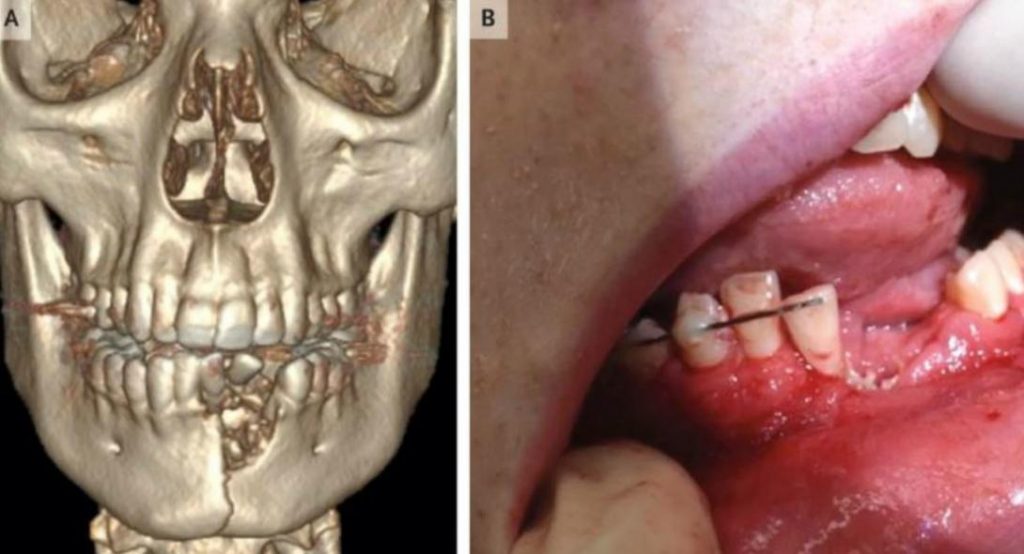

Ειδικότερα, σύμφωνα με τη σχετική έκθεση της ιατρικής επιθεώρησης «The New England Journal of Medicine», ο άτυχος 17χρονος έφτασε στα επείγοντα του νοσοκομείου του Σολτ Λέικ Σίτι στις ΗΠΑ, με εκτεταμένα τραύματα στο στόμα, με σπασμένη κάτω γνάθο κι αρκετά από τα δόντια του να λείπουν.

Οι γιατροί χρειάστηκε να αφαιρέσουν αρκετά δόντια από τον έφηβο, ενώ του τοποθετήθηκε και ειδικό εμφύτευμα, προκειμένου να του σταθεροποιηθεί το οστό του σαγονιού.

Επειδή όμως το σαγόνι του εφήβου δεν έκλεινε σωστά, οι γιατροί αποφάσισαν να του το δέσουν, ώστε το στόμα του να παραμείνει κλειστό για 6 εβδομάδες.

Έτσι και μόνο έτσι θα μπορούσε το κάταγμά του να επουλωθεί.